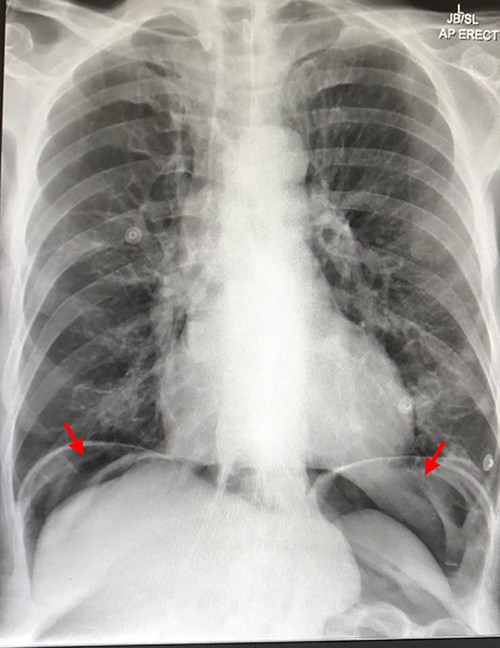

Chest X-ray showing air under the diaphragm suggestive of pneumoperitoneum (red arrows)

On presentation, his temperature was 37.8°C, and he was hypotensive at 100/45 mmHg and tachypneic with a respiratory rate of 22. He was in moderate respiratory distress and was placed on 2 L oxygen via nasal prongs. On abdominal examination, mild distension was noted with lower abdominal tenderness with rebound tenderness and guarding in the right lower quadrant. He had normal leukocytes of 5 × 109 /L (N: 4.0–11 × 109/L) and lactate was normal at 1.6 mmol/L (N: 0.5–2.2 mmol/L). X-ray chest showed free air under the diaphragm suggestive of pneumoperitoneum (Fig. 1). A CT abdomen was performed showing large-volume free air suggestive of a viscous perforation and moderate volume of free fluid in the abdomen (Fig. 2). The site of perforation was not confidently established on the study. There was generalized oedema of the right side of the colon with multiple loops of dilated small bowel. His Physiological and Operative Severity Score for enumeration of Mortality and Morbidity (POSSUM) score would be 81% predicted mortality and 98.8% predicted morbidity if he were to undergo an emergent laparotomy operation. Family discussion was made, and he decided not to proceed with operative management. He was managed conservatively with piperacillin-tazobactam and decompressed with nasogastric tube insertion. As the days progressed, his abdomen became increasingly distended and tympanic, but not peritonitic. We repeated a CT chest and abdomen three days after initial admission and it was reported he had tension pneumoperitoneum (Fig. 3). CT with oral contrast was also performed to exclude an upper GI perforation.